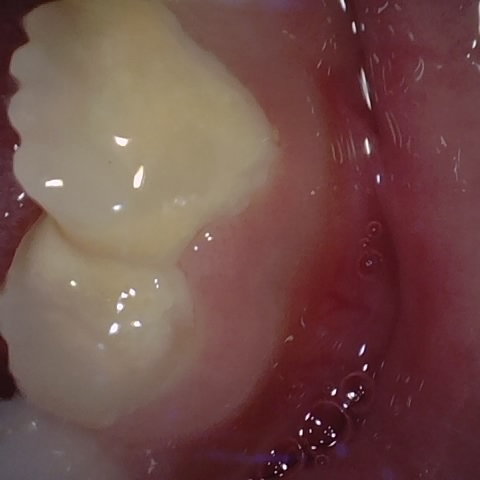

Annotated as "Good"

Original Image Rendering Image